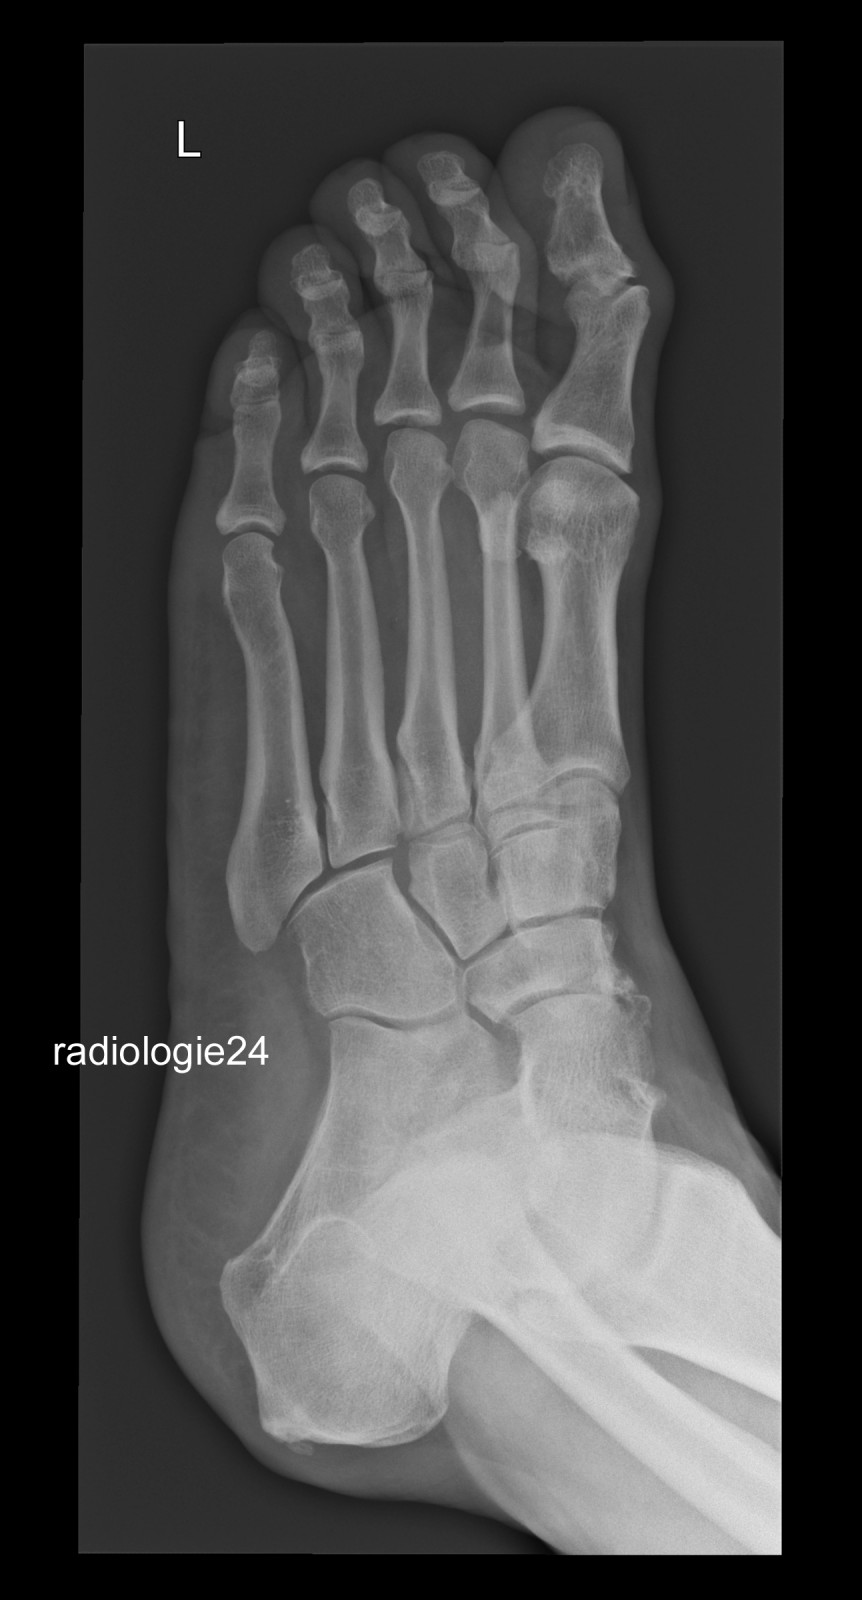

Röntgenfall des Monats September 2018 mit Auflösung

52 jähriger Patient

Fehltritt beim Wandern. Schmerzen Mittelfuss.

Ihre Diagnose? Weitere radiologische Diagnostik notwendig?